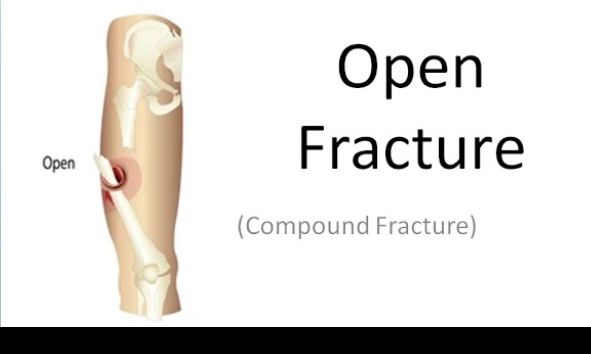

Open (compound) fractures

Open wounds with exposed bone

Bleeding after injury